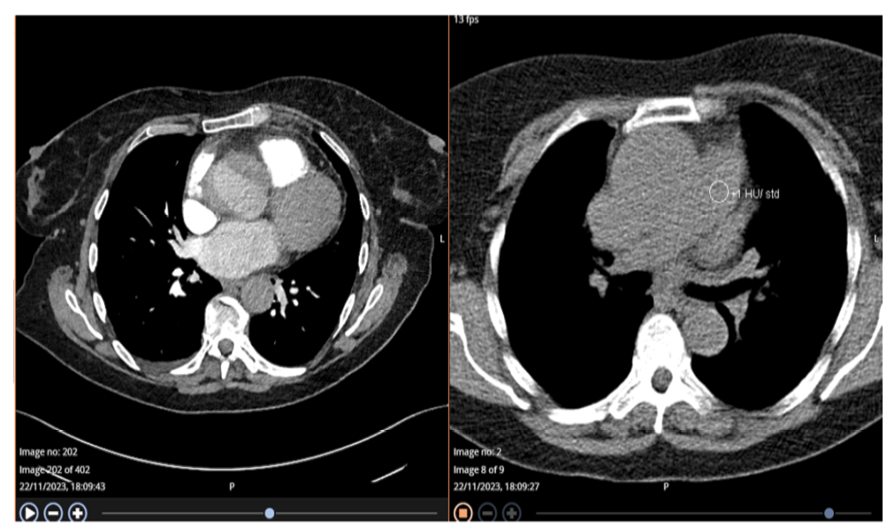

The patient was treated with Tazocin and IV fluids and had a CT scan that showed dilation of the common bile duct (CBD), no visible stones, and fluid surrounding the gallbladder along with mild thickening (Figure-1-A). These findings were indicative of acute acalculous cholecystitis, along with unexpected cardiac issues, such as an ascending aortic aneurysm and cardiomegaly (Figure-1-B). Further evaluation shifted the focus to her cardiac conditions, as the CT results regarding the gallbladder could also be influenced by heart failure.

Figure 1-A-B. First CT Angiography to rule out pulmonary embolism (PE) showed dilated Ascending Aorta with a dissection flap that can be seen in the retrospective analysis and no evidence of PE.